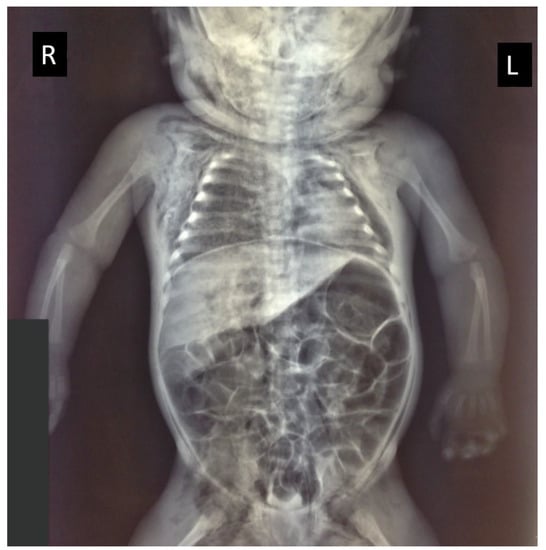

The chest X-ray confirmed the absence of skeletal injuries and revealed a large pneumothorax, with a collapsed left lung and a mediastinal shift (Figure 2).

Figure 2. Radiological investigations demonstrated skin emphysema on the right and left side of the neck, the thorax, and in the groin area, with a large left-sided pneumothorax and compression of the collapsed lung (R = right side; L = left side) and a bloating intestine.